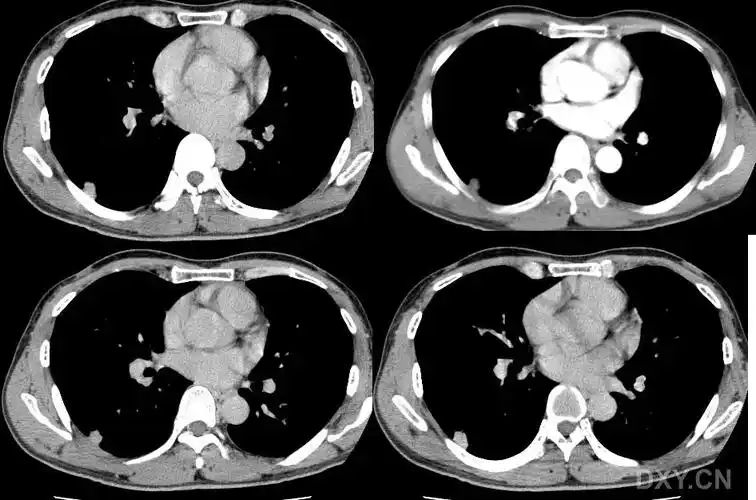

图片是患者ct平扫和多期增强扫描(动脉期,静脉期,平衡期或延迟期)的

胸部ct平扫示左下肺占位肺癌